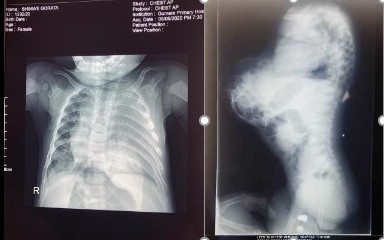

Rayos x de tórax. Ausencia del corazón en su posición en el tórax. Silueta cardíaca aumentada, borramiento de hemidiafragma derecho, infiltrado difuso de aspecto inflamatorio en ambos campos pulmonares e imagen radiopaca abdominal correspondiente el corazón del paciente (figura 2)La madre se negó a realizar la Tomografía Axial Computarizada (TAC).El ultrasonido determinó una hernia diafragmática,las vísceras abdominales de tamaño normal, y presencia del corazón con los grandes vasos en plena actividad.